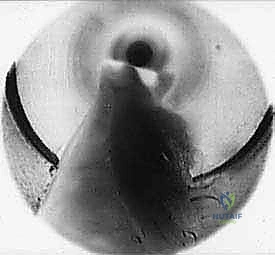

3. إدخال الكانيولا والمنظار:

يتم إدخال أداة مجوفة دقيقة (Cannula) عبر الشق الصغير، وتوجيهها بحذر شديد تحت الجلد وفوق الرباط المستعرض (TIML). بعد ذلك، يتم إدخال كاميرا المنظار (Endoscope) الدقيقة (عادة بقطر 2.7 ملم أو 4 ملم) عبر الكانيولا.

4. الرؤية المكبرة وتحديد الرباط:

تُعرض الصورة المكبرة بدقة 4K على شاشة أمام الجراح. يقوم الدكتور هطيف بتنظيف الأنسجة الدهنية الدقيقة برفق باستخدام أدوات متخصصة حتى يظهر الرباط المستعرض (TIML) بوضوح تام، وتظهر أليافه العرضية المميزة.

5. تحرير الرباط وتخفيف الضغط (The Release):

هذه هي الخطوة الأكثر دقة. باستخدام سكين جراحي دقيق مخصص للمناظير (Hook knife أو سكين رجعي)، يتم إدخاله تحت أو فوق الرباط. وبحركة دقيقة ومحسوبة، يقوم الدكتور هطيف بقطع الرباط المستعرض بالكامل من النهاية القريبة إلى النهاية البعيدة.

6. تأكيد التحرير:

بمجرد قطع الرباط، تتسع المسافة بين رؤوس الأمشاط فوراً. يقوم الدكتور هطيف بفحص المنطقة بالمنظار للتأكد من القطع الكامل للرباط، والتأكد من أن العصب تحرر تماماً من الضغط، مع التأكد من سلامة الأوعية الدموية المجاورة.